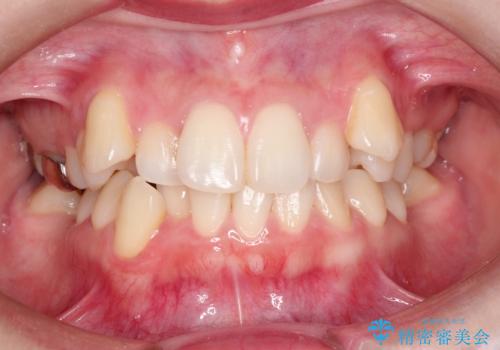

大臼歯の欠損をインプラントを使わず矯正で閉鎖|親知らずの活用による咬合改善

- 20代女性

最終的には予定通りインプラントを使用せずに欠損部を閉鎖し、咬合も安定させることができました。